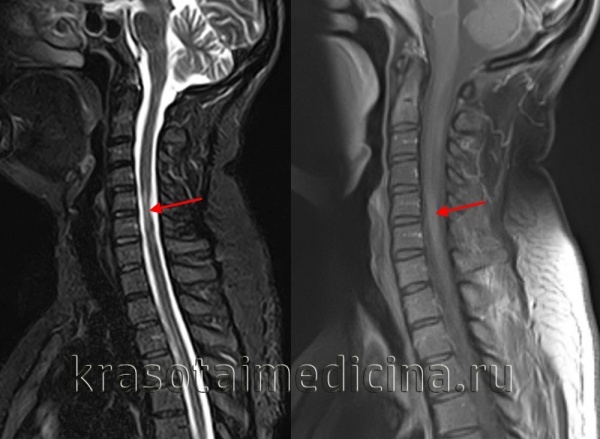

Информация о диссеминированном рассеянном энцефаломиелите